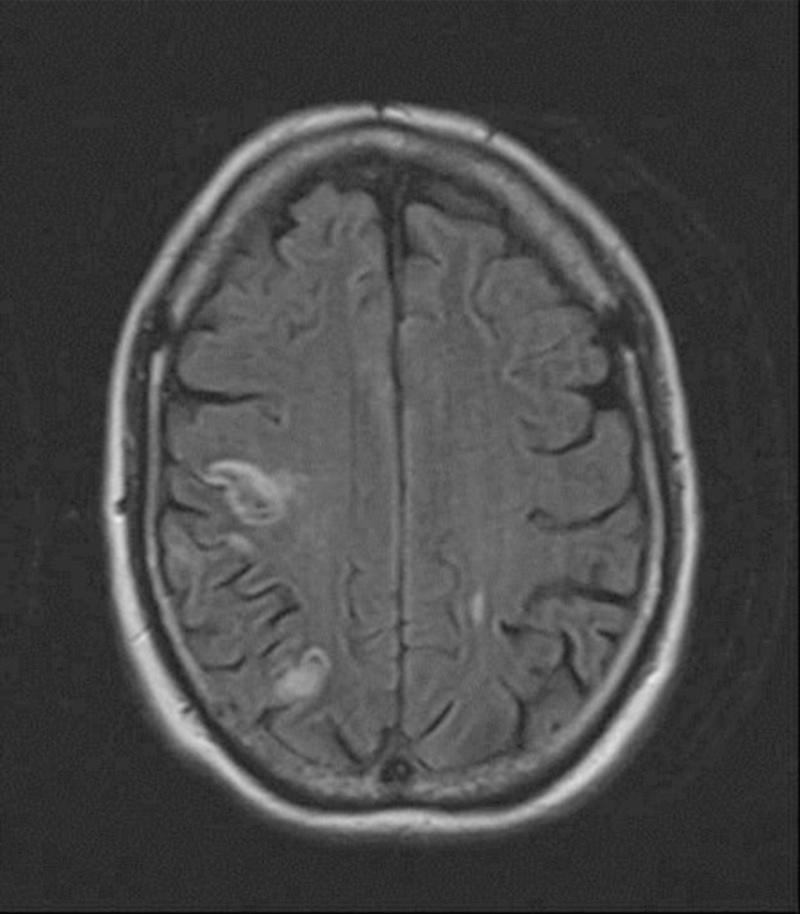

Granulomatosis with polyangiitis presenting as ischaemic stroke.

https://cdn.ncbi.nlm.nih.gov/pmc/blobs/6492/3545330/26dcd89dde81/SHORTS-12-01101.jpg

Granulomatosis with polyangiitis presenting as ischaemic stroke.以缺血性卒中为表现的肉芽肿性多血管炎。